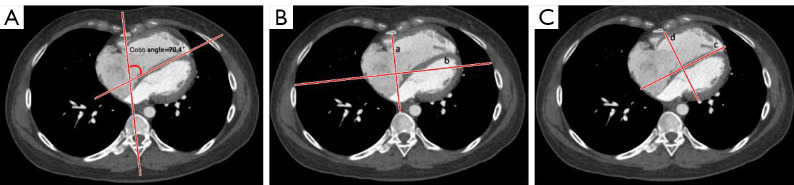

Methods: Data from PH patients who underwent CTPA, TTE, and right heart catheterization (RHC) were analyzed retrospectively. The Cobb angle, defined as the angle between the spine and interventricular septum, was calculated by CTPA. It is assumed that thorax geometry, pericardial morphology, and body surface area (BSA) are factors influencing the Cobb angle measurement, and these factors were adjusted for in the analysis. Multiple linear regression was performed to evaluate the multivariate ability to predict PVR. Multivariate Cox regression analysis assessed the prognostic value of parameters in predicting hospitalization for heart failure.

Results: In total, 78 patients meeting the criteria were enrolled. Among the TTE parameters, the right ventricular outflow tract acceleration time (RVOT-AT) demonstrated the best goodness-of-fit to PVR (R2=0.433, P<0.001). Correcting the Cobb angle by BSA significantly improved its fit to PVR (R2=0.510, P<0.001), compared to the uncorrected angle (R2=0.450, P<0.001). The model combining Cobb angle/BSA and RVOT-AT strongly predicted PVR (r=0.815, R2=0.634, P<0.001) and was effective across different demographics. After multivariable adjustment, the Cobb angle [hazard ratio (HR): 1.057; P<0.001], Cobb angle/BSA (HR: 1.087; P<0.001), tricuspid annular plane systolic excursion (TAPSE) (HR: 0.878; P=0.014), RVOT-AT (HR: 0.968; P=0.030), and right ventricular myocardial performance index (RVMPI) (HR: 5.324; P<0.001) remained significant independent predictors of heart failure.